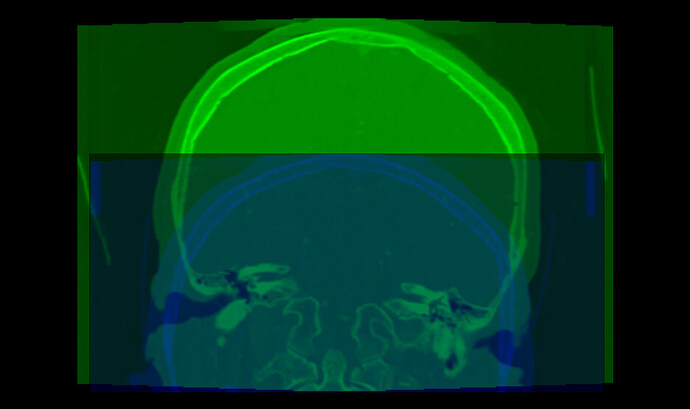

Your images have several strange properties, any of them may can cause an automatic intensity-base image registration methods to struggle:

• Most registration methods generally require the images cover the same region. Your images do not meet this requirement. To fix this, probably the easiest is to crop the images to approximately to the same region.

• The image edges coincide edge of anatomy (skull touches the image edge). This is an issue because image processing methods often need to extrapolate a little bit beyond the image region and this extrapolation will fail if the intensity near the image edge is non-uniform (it is fine if the image edge cuts through the middle of tissue or cuts through the middle of air, but the image edge should not be at an anatomical region boundary).

Interesting. For me, Elastix registered the images you shared with the rigid preset.

result: